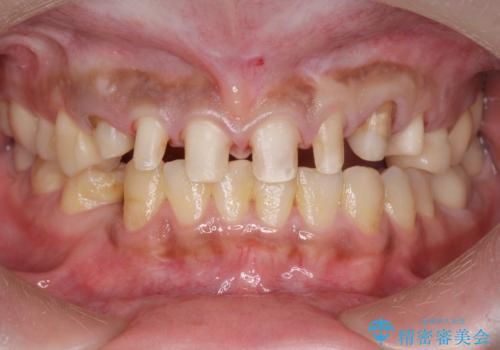

複数箇所コンポジット充填された前歯をセラミック治療

- コンポジットレジンの充填箇所がすり減ってしまい、形の悪くなった前歯の治療を希望され来院されました。

充填部位が大きく、再度充填をするには神経と近くなり抜髄のリスクが高まるため、劣化の少ないセラミックでフルカバーするセラミッククラウン治療を行うこととしました。

前歯の小さな虫歯は、除去したのちコンポジットレジンと言われる樹脂を充填する処置を行うことが多々あります。

しかし、経年劣化が早く着色や小さな虫歯が再発しやすいため、ある程度の大きさになってしまった場合セラミッククラウンで置き替えた方が神経を温存し長期的な予後の期待できる治療となります。